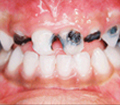

A Case of Rampant caries (Nursing bottle caries)